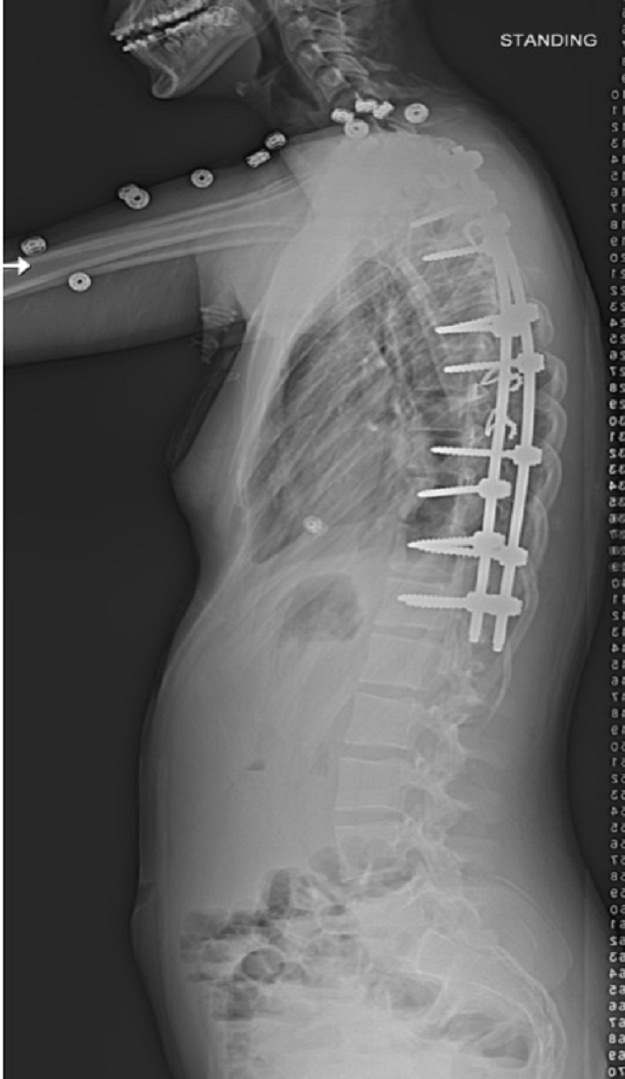

Posterior Spinal deformity correction and instrumented fusion surgery|Pune Spine Institute|Spine clinic in pune Spine centre in pune, Spine hospital in pune, Spine care in pune

Patient was treated with Posterior Spinal deformity correction and instrumented fusion surgery to correct the scoliosis.